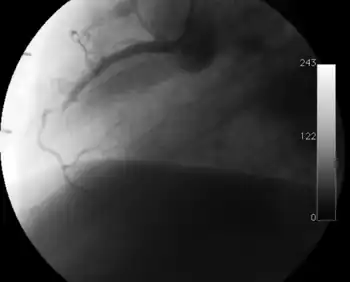

Coronary angiography

Surveillance is performed by regularly repeating coronary angiography in the cardiac catheterization laboratory, the diagnostic test of choice.[2] This is typically performed annually for the first five years after transplantation.[8] Angiography in CAV characteristically demonstrates diffuse stenoses in large coronary arteries and a reduced number of smaller coronary arteries, also known as "peripheral pruning".[2][6] However, because CAV frequently affects the entire length of the coronary artery, CAV may not be apparent by angiography alone.[2]

-

Occlusion of the right coronary artery 2 years after heart transplantation. -